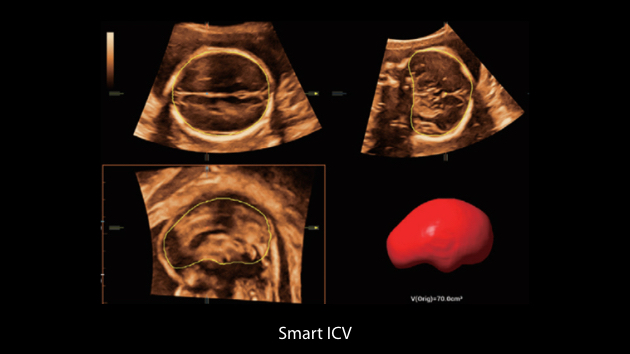

Nuewa I9 Elite Edition ├© progettato appositamente per l'assistenza sanitaria a donne e neonati e offre un'esperienza innovativa sviluppata sulla base di conoscenze approfondite relative a scenari clinici complessi, per risposte accurate e tempestive, nonch├® un'efficienza e un'esperienza utente eccezionali